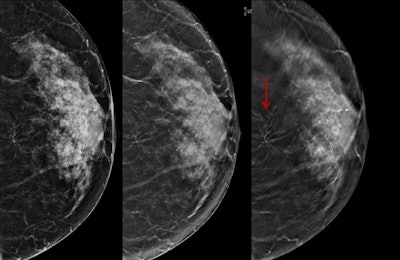

Single-reading digital breast tomosynthesis (DBT) plus synthesized 2D mammography increased cancer detection and decreased recalls compared with double-reading standard mammography in a new study, published online by European Radiology on 2 January. In addition, standard mammography did not improve results when added to DBT.

Standard 2D mammography is the usual breast cancer screening technique, but experts continue to question whether DBT is up to the task as standard mammography has some limitations. DBT increases cancer detection and decreases recalls but amplifies radiation dose when added to 2D. Using synthesized 2D mammography -- or reconstructing a 2D mammogram using DBT data -- helps overcome the radiation dose, but DBT also has a higher cost and a longer interpretation time.

The researchers observed no significant differences in cancer detection or recall rates between DBT plus synthesized and DBT plus synthesized plus 2D. Nor did they observe any improvement when 2D mammography was added to DBT plus synthesized, which could avoid the performance of 2D.